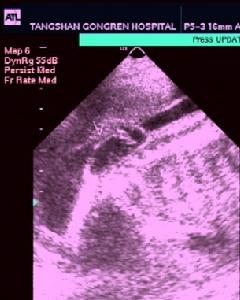

頸部囊狀淋巴管瘤1、頸後三角區囊性腫塊,具有向四擊(鎖骨上下、口底、氣管食管旁及縱隔)蔓延生長特點,界限常不清楚。多見於嬰幼兒。出生時即呈巨大,亦可逐漸長大。

2、囊瘤柔軟,一般無壓縮性,能透光。表麵皮膚正常,不粘連。

3、內容物淡黃透明或乳糜狀,偶帶血性。鏡下可見大量含有膽固醇結晶的淋巴細胞。

4、囊瘤較在累及口底、舌或咽部時,可有語言、呼吸或吞咽障礙。囊瘤位於鎖骨上時,可有臂叢受壓出現運動障礙或肌肉萎縮。有時氣管受壓移位。